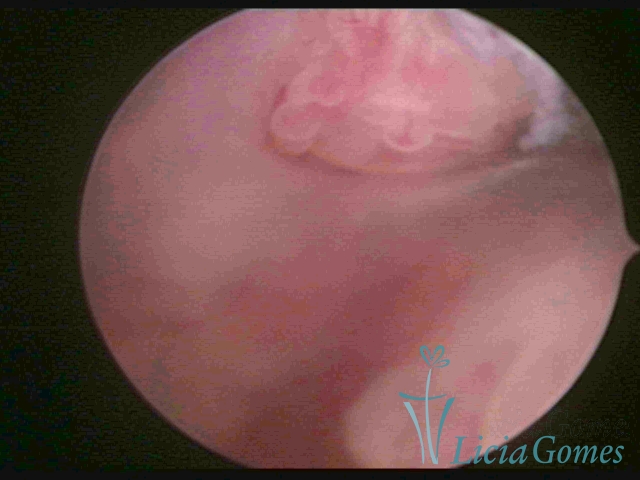

PÓLIPOS ENDOCERVICAIS

São tumores benignos, resultantes da proliferação focal reativa aos processos inflamatórios ou à situações de hiperestrogenismo, e podem ter sésseis (com a base de implantação larga) ou pediculados do epitélio.